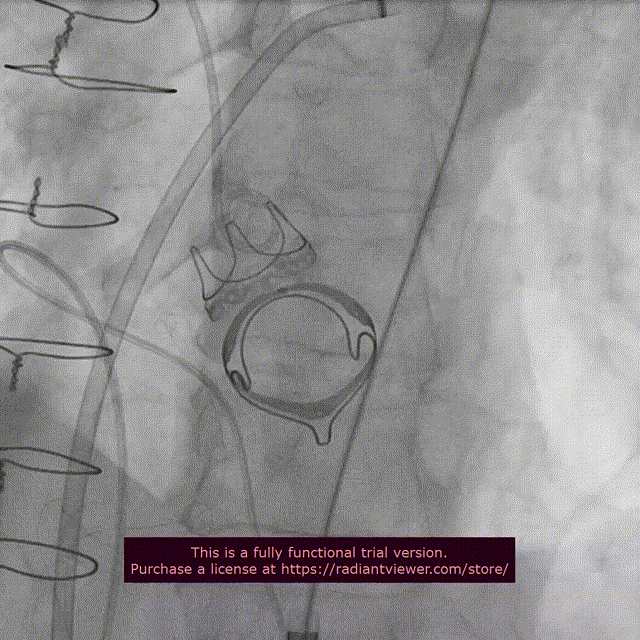

5.主动脉瓣位植入20mm SAPIEN 3瓣膜,球囊体积增加2cc

释放后瓣膜形态

10. 双瓣植入后左室造影与主动脉根部造影

双瓣SAPIEN 3瓣膜植入后主动脉根部造影

二尖瓣位和主动脉瓣位SAPIEN 3瓣膜功能良好

二尖瓣位SAPIEN 3瓣膜不影响左室流出道